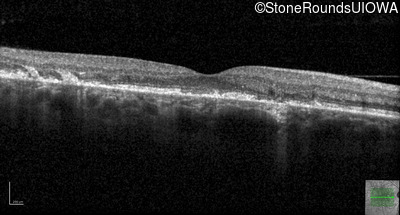

Age at visit: 49 years

Age at visit: 49 years (Visit 2)